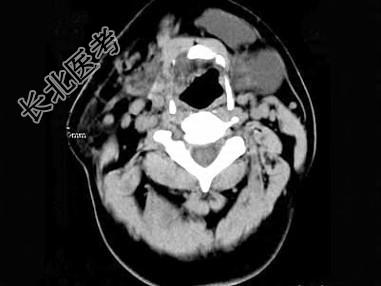

- 单项选择题男,32岁, 左侧下颌部肿块,CT如图所示, 最可能的诊断是 ( )

A、造釉细胞瘤

B、颌骨囊肿

C、鳃裂囊肿

D、颈部淋巴管瘤

E、舌下腺囊肿